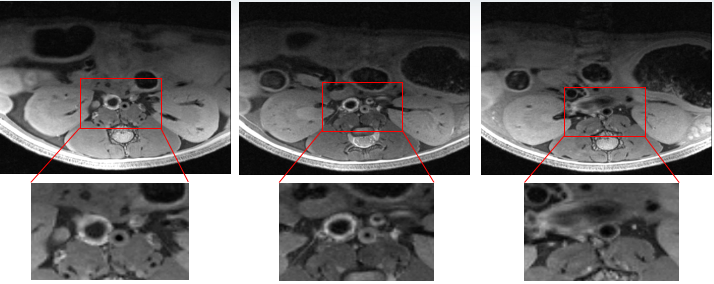

图10 高分辨率双肾成像